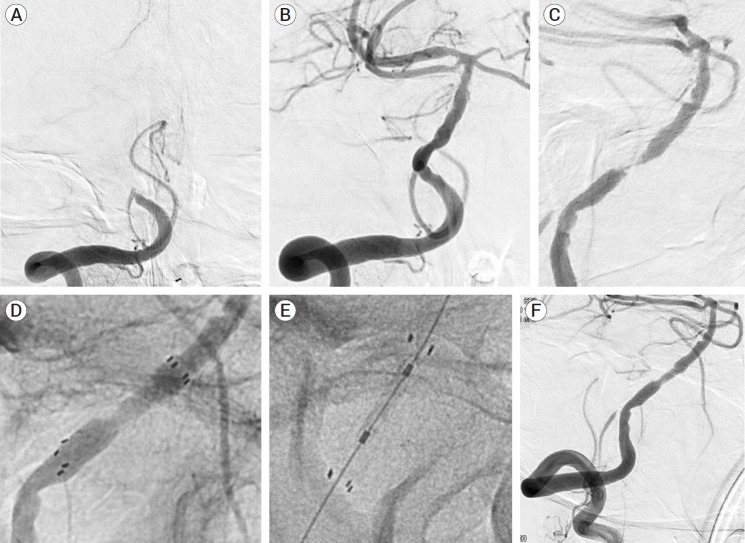

Results: Compared to those without rescue procedures, RAS group had a higher percentage of large artery atherosclerosis as an etiology (p<0.001), long segment occlusions (p=0.03), and was more likely to involve posterior inferior cerebellar artery (p=0.007). There was no difference in functional outcome at 6 months between these two groups. Reopening could not achieve (N=2, 13.3%) and procedural complication rate (iatrogenic rupture) is 6.7% in RAS group. Rescue procedures were complicated with dissection, plaque rupture and migration, device damage, and misplacement of the balloon/stent. Avoiding these traps, finding true lumen, and reconstructing the flow by connecting the proximal and distal normal were the keys to the successful RAS.

Conclusions: RAS could be inevitable during endovascular treatment for PCIS and being aware of possible events and technical strategies would navigate interventionists to successful recanalization and the better outcomes.